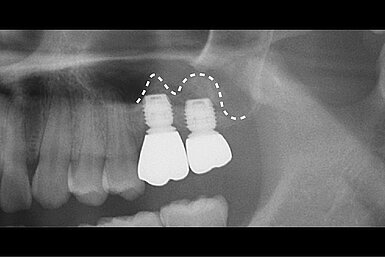

Geistlich Usa Crestal Sinus Floor Elevation Background this study evaluated the clinical and radiographic outcomes of using demineralized dentin matrix (ddm) as a graft material at the implant apex during crestal sinus floor elevation. we hypothesized that ddm would promote predictable bone regeneration at the sinus floor and facilitate implant stability with minimal surgical morbidity. methods a retrospective analysis was performed on. This clinical case, with 12 month follow up, showed the employment of geistlich bio oss® and geistlich bio gide® in sinus floor elevation for the purpose of rehabilitation with dental implants. No significant sinus complications or graft failures occurred. within the limitations of this retrospective study, crestal sinus elevation with ddm grafting at the implant apex proved to be a safe and effective minimally invasive technique, consistently yielding bone regeneration and excellent implant survival in the posterior maxilla. pmid. This study encourages the crestal approach to sinus elevation, even in patients with less than 4 mm of residual bone height. the postoperative radiograph and the three year follow up showed a significant increase in vertical bone height that remained stable over time. This technique involves accessing the sinus through the alveolar ridge at the intended implant site. a small opening is created in the crestal bone, and specialized instruments are used to gently apply controlled vertical pressure, fracturing the sinus floor while preserving membrane integrity. Dr. rui figueiredo places the implant before completely filling the sinus with geistlich bio oss® granules (delivered by the geistlich bio oss pen®).

Geistlich Usa Crestal Sinus Floor Elevation No significant sinus complications or graft failures occurred. within the limitations of this retrospective study, crestal sinus elevation with ddm grafting at the implant apex proved to be a safe and effective minimally invasive technique, consistently yielding bone regeneration and excellent implant survival in the posterior maxilla. pmid. This study encourages the crestal approach to sinus elevation, even in patients with less than 4 mm of residual bone height. the postoperative radiograph and the three year follow up showed a significant increase in vertical bone height that remained stable over time. This technique involves accessing the sinus through the alveolar ridge at the intended implant site. a small opening is created in the crestal bone, and specialized instruments are used to gently apply controlled vertical pressure, fracturing the sinus floor while preserving membrane integrity. Dr. rui figueiredo places the implant before completely filling the sinus with geistlich bio oss® granules (delivered by the geistlich bio oss pen®).